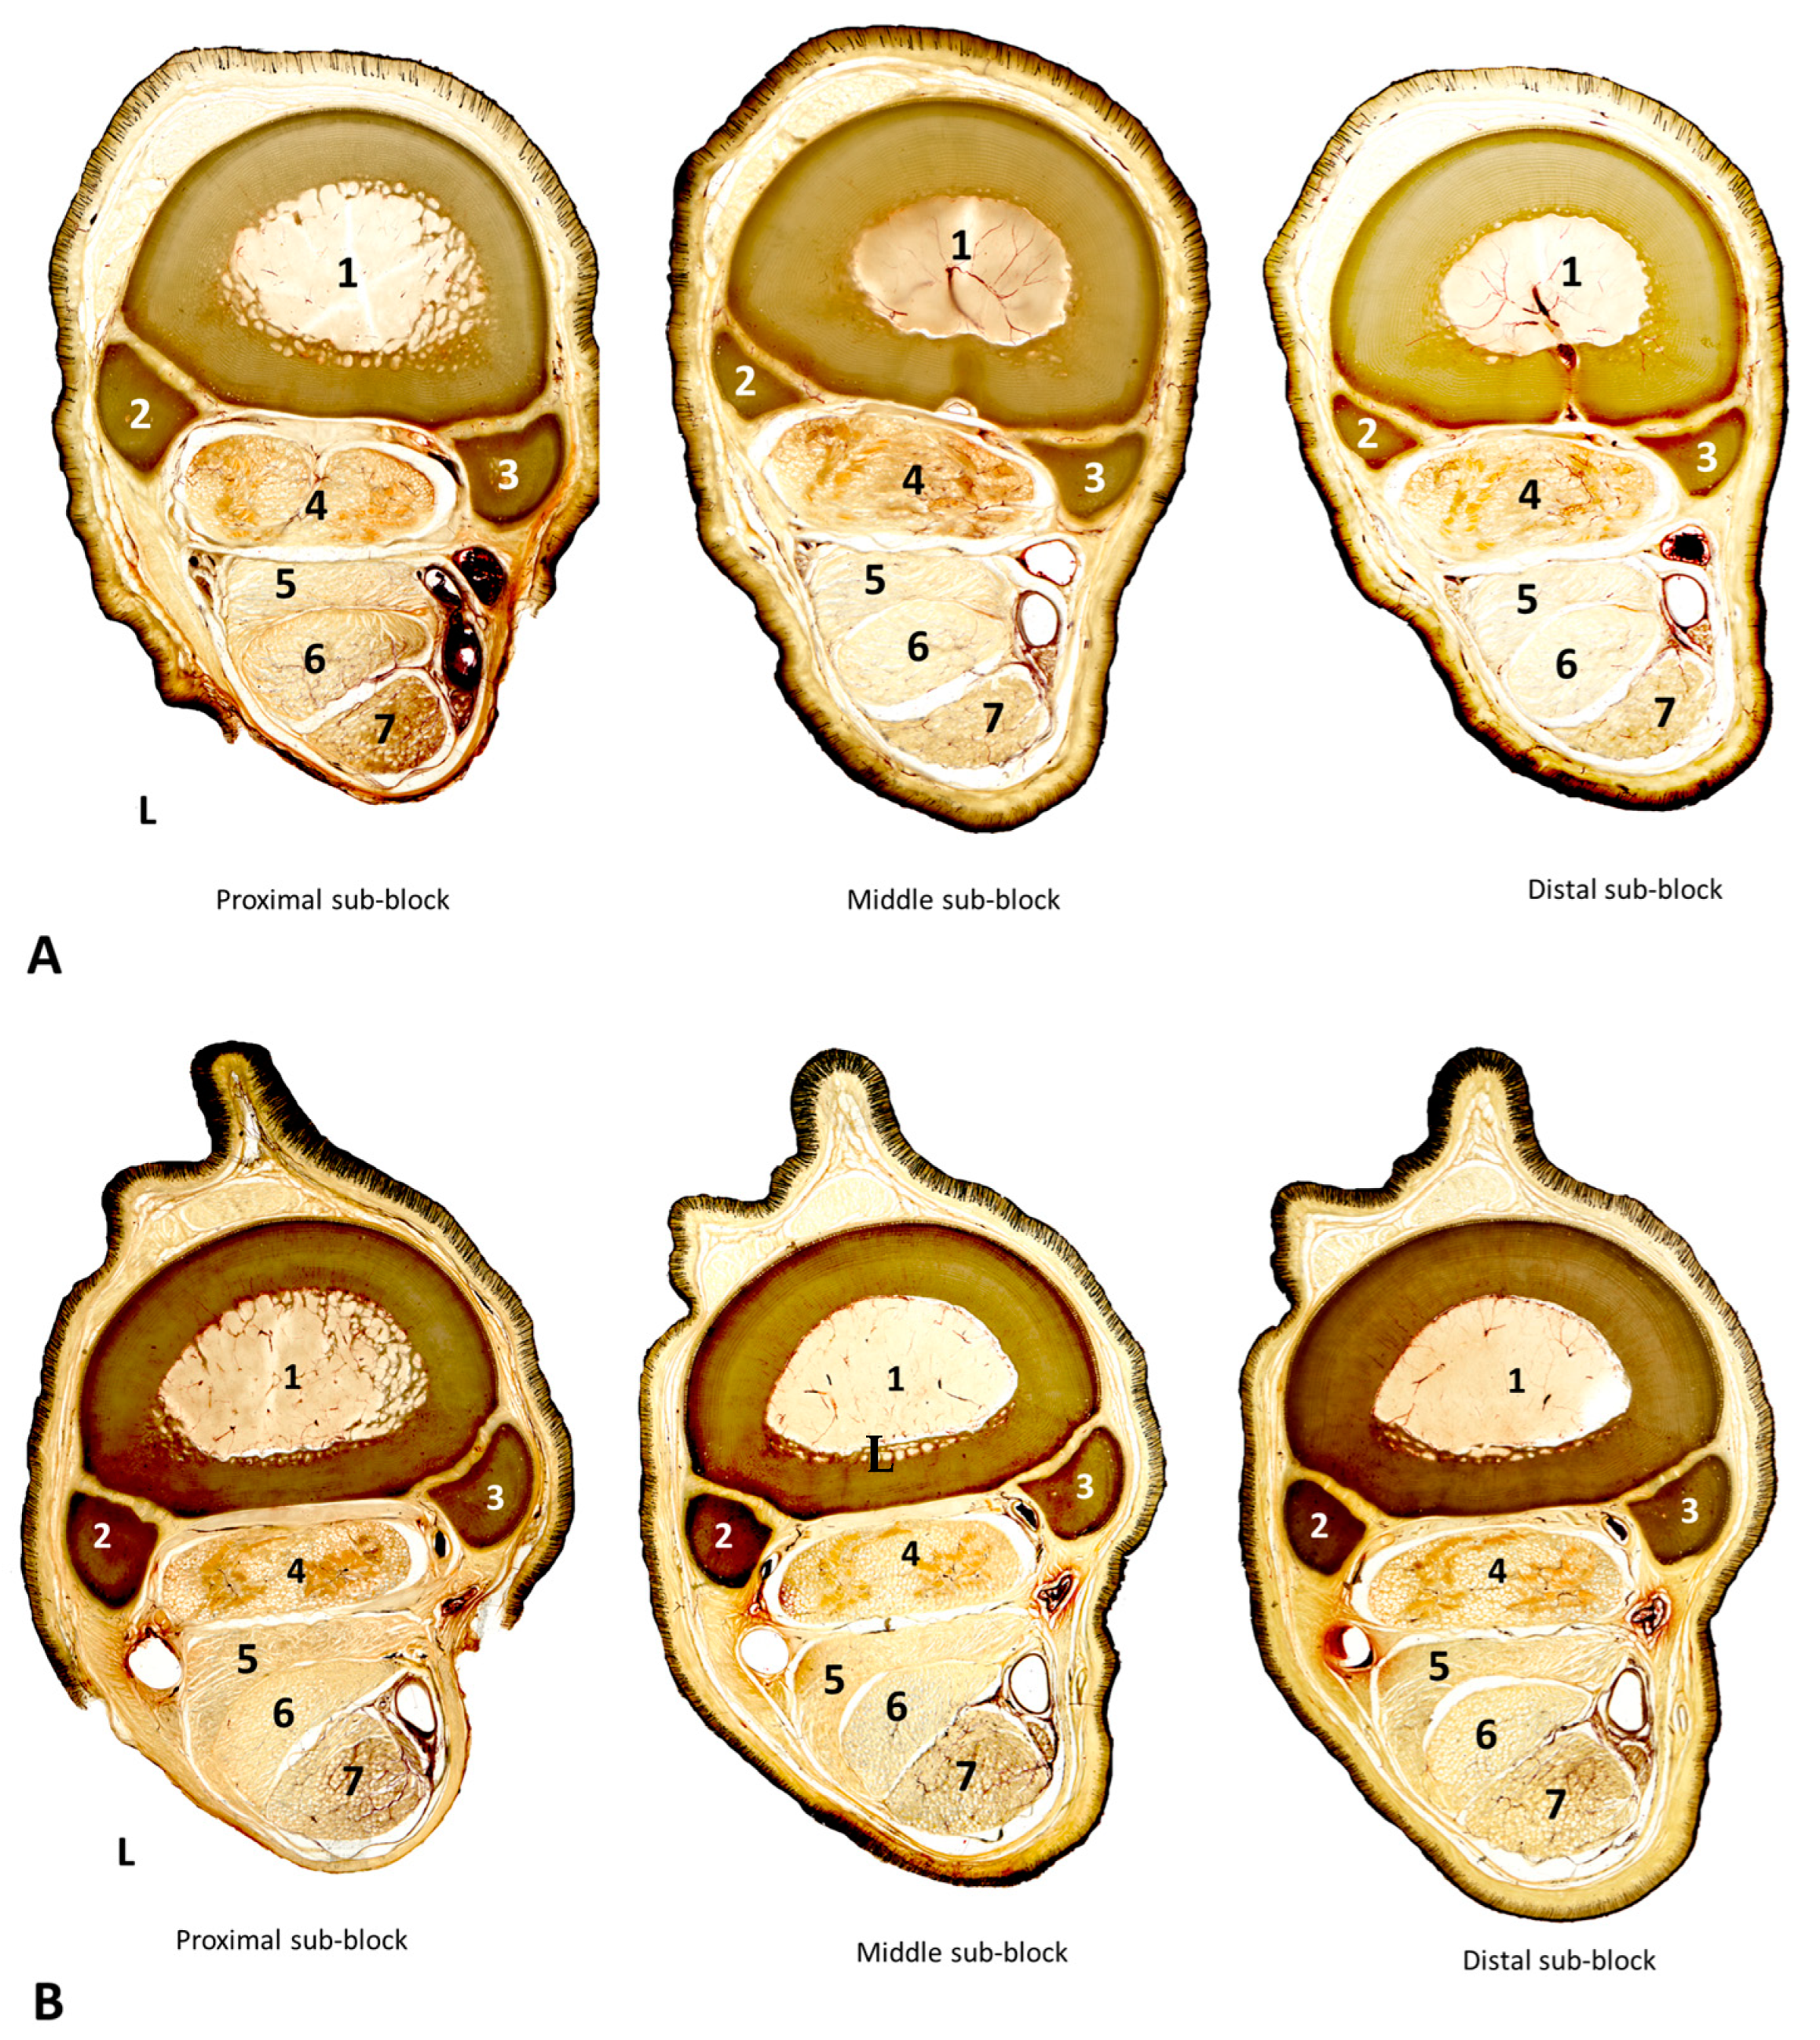

3.2. Cross-Sectional Anatomy

3.3. Morphometric Analysis